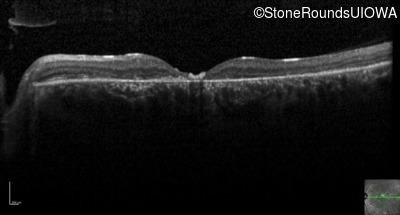

Optical Coherence Tomography - Left - 20/200

Exemplar / OCT Stack